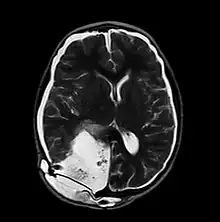

MRI of Pseudomeningocele in 8 years old male patient | |

A pseudomeningocele is an abnormal collection of cerebrospinal fluid (CSF) that communicates with the CSF space around the brain or spinal cord. In contrast to a meningocele, in which the fluid is surrounded and confined by dura mater, in a pseudomeningocele, the fluid has no surrounding membrane, but is contained in a cavity within the soft tissues.